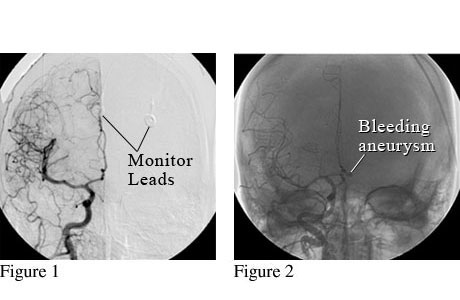

Head Angiogram